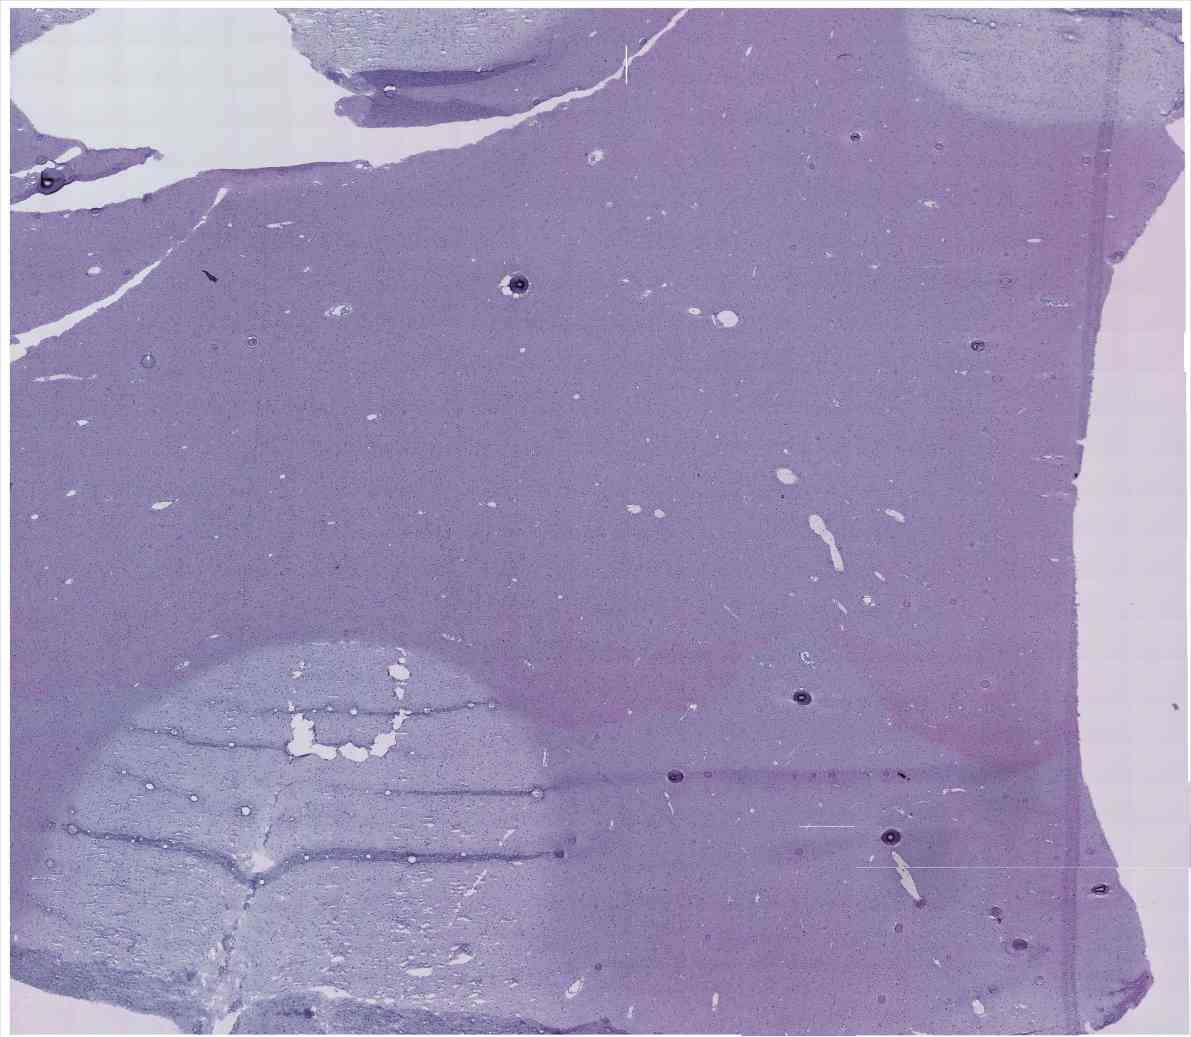

Chip 014 Well E2